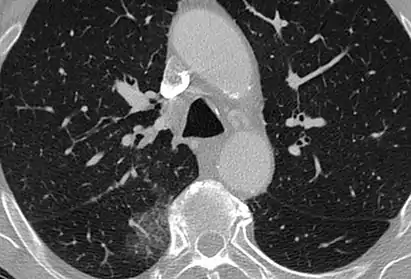

CT image showing diffuse GGOs throughout both lungs. An abscess is also noted in the right lung (screen left). - Adenocarcinoma in situ of the lung

The diffuse pattern typically refers to GGOs in multiple lobes of one or both lungs. Broadly, a diffuse pattern of GGO can be caused by displacement of air with fluid, inflammatory debris, or fibrosis. Cardiogenic pulmonary edema and ARDS are common causes of a fluid-filled lung. Diffuse alveolar hemorrhage is a rarer cause of diffuse GGO seen in some types of vasculitis, autoimmune conditions, and bleeding disorders.[6]

Inflammation and fibrosis can also cause diffuse GGOs. Pneumocystis pneumonia, an infection typically seen in immunocompromised (e.g. patients with AIDS) or immunosuppressed individuals, is a classic cause of diffuse GGOs. Many viral pneumonias and idiopathic interstitial pneumonias can also lead to a diffuse GGO pattern. Radiation pneumonitis, a side effect of pulmonary radiation therapy, can lead to pulmonary fibrosis and diffuse GGOs.[6]